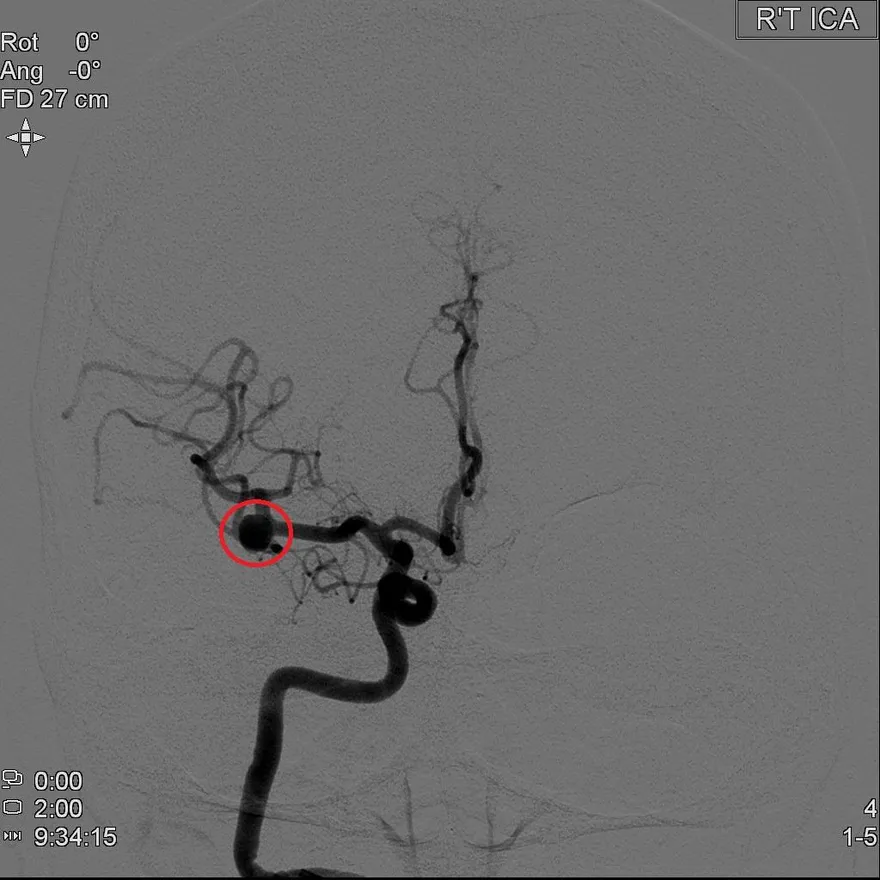

動脈瘤

核磁共振

血管